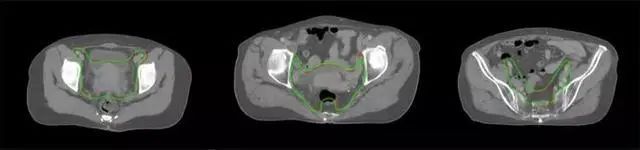

四、放射治療智能勾畫軟件

放射治療,簡稱放療,是治療腫瘤主要手段之一,利用放射線破壞照射區(qū)(靶區(qū))的細(xì)胞,使腫瘤細(xì)胞停止分裂直至死亡,醫(yī)生通常把放射治療形象的比喻為“打靶”,放療前精準(zhǔn)勾畫腫瘤靶區(qū)范圍是腫瘤放射治療的關(guān)鍵步驟。傳統(tǒng)的靶區(qū)勾畫醫(yī)生會根據(jù)患者多張CT、MRI影像片憑借經(jīng)驗(yàn)進(jìn)行,比較耗時(shí),治療的病人數(shù)量也有限,且靶區(qū)勾畫缺少行業(yè)統(tǒng)一的規(guī)范和標(biāo)準(zhǔn),無法達(dá)到同質(zhì)化,勾畫精確度不理想。

技術(shù)原理

基于深度學(xué)習(xí)人工智能的放療靶區(qū)智能勾畫技術(shù)和自動(dòng)計(jì)劃技術(shù),基于全面的市場調(diào)研和臨床專業(yè)意見,采用獨(dú)創(chuàng)的基于小樣本量的人工智能算法,實(shí)現(xiàn)放療靶區(qū)和危及器官的快速全自動(dòng)勾畫。

產(chǎn)品優(yōu)勢

縮短至幾分鐘內(nèi)便可完成,大幅提升了放療效率,且人工智能平臺完成的靶區(qū)勾畫可基本滿足臨床醫(yī)生需求,專家只需審核時(shí)細(xì)微調(diào)整,可顯著提高靶區(qū)勾畫的規(guī)范化及精準(zhǔn)度,讓放療智能化,標(biāo)準(zhǔn)化??筛采w食管癌、鼻咽癌、直腸癌、宮頸癌、肺癌等多種病種。